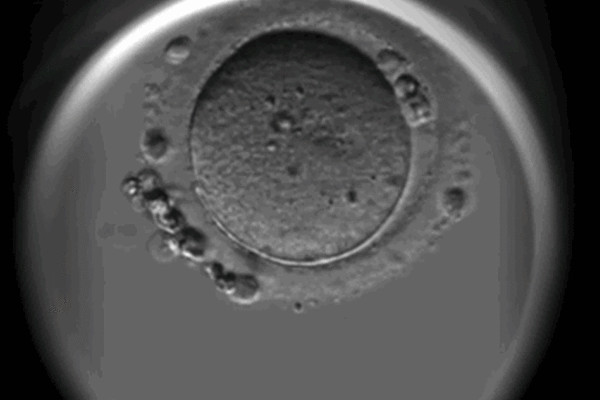

進行第三代試管嬰兒治療時,宮腔鏡是一個常見的輔助性檢查方法,通過宮腔鏡可以詳細觀察子宮內部情況,並幫助醫生判斷及解決可能影響胚胎著床和發育的問題,評估子宮內膜厚度和質量,增大試管移植的成功率。評估子宮內膜厚度和質量:子宮內膜是胚胎著床及發育所需的重要環境之一,通過宮腔鏡可以直接觀察子宮內膜的厚度和質量,確定是否適合胚胎著床;發現子宮內畸形或息肉等異常情況:有些女性可能存在子宮內畸形或者子宮內腔中的...

對於試管鮮胚移植不成功的女性來說,需要在生化妊娠後宮腔鏡或者免疫全套檢查,因為利用這兩項檢查可以檢查宮腔內部環境是否存在異常、子宮內膜是否存在粘連或其他不良情況,另外,在檢查後不僅可以找出鮮胚移植失敗的原因,還可以對症治療,避免下一次移植失敗,提高二次移植的試管成功率。宮腔鏡檢查就是利用宮腔鏡檢視患者子宮腔內的情況,並對宮腔內疾病進行診斷和治療,還可以清晰的觀察到宮腔內的各種改變,免疫全套檢查主要...

前一個月做完宮腔鏡檢查移植的時候成功率是會有所提高,宮腔鏡檢查的結果對於試管嬰兒移植的成功率有著直接的影響,修復或去除子宮問題可以增加子宮內膜的接受性,從而提高胚胎成功植入的機會,此外,研究表明,宮腔鏡檢查還可以改善子宮內膜的血液供應,提高胚胎著床的機會。在輔助生殖技術(如試管嬰兒)中,宮腔鏡檢查被用於評估子宮內膜的健康,移除可能存在的障礙物,從而有助於提高移植胚胎成功率,以下是宮腔鏡檢查能提高移...